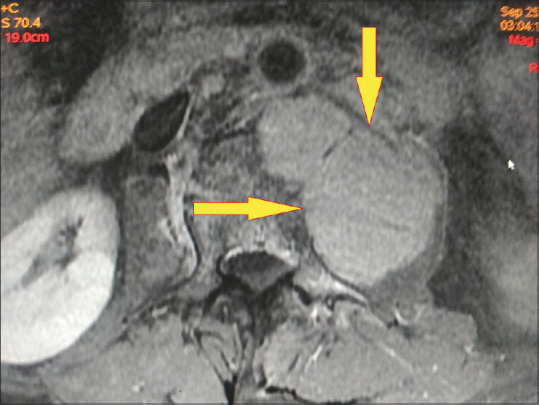

霍奇金淋巴瘤合并结核病是一种极为罕见的临床病例,由于临床表现相似,因此很难处理。本病例报告描述了一名 44 岁男性患者的相同情况,该患者被诊断为科氏淋巴瘤,并在脊柱活检和培养结果证实的基础上开始接受抗结核治疗。尽管接受了结核病治疗,但患者的临床症状仍在恶化。因此,对患者进行了进一步检查,包括纵隔镜检查和支气管内超声检查。从下颈部和纵隔内的聚集性肿块中提取的活检样本显示为结节性硬化型霍奇金淋巴瘤。在接受化疗和放疗以及抗结核治疗后,患者的病情有了明显好转。

Concomitant Hodgkin's lymphoma with tuberculosis is an exceedingly rare clinical scenario and a condition that is difficult to manage due to similar clinical presentation. This case report describes the same in a 44-year-old male patient diagnosed with Koch's and initiated on antituberculosis therapy, based on confirmation of findings from the spine biopsy and culture. The patient's clinical condition worsened despite being on treatment for tuberculosis. Hence, further work up of the patient was done which included mediastinoscopy and endobronchial ultrasound. Biopsy samples from a conglomerate mass in the lower cervical region and mediastinum revealed Hodgkin's lymphoma of the nodular sclerosis type. This time, the patient showed significant improvement following treatment with chemotherapy and radiotherapy along with antituberculosis therapy.